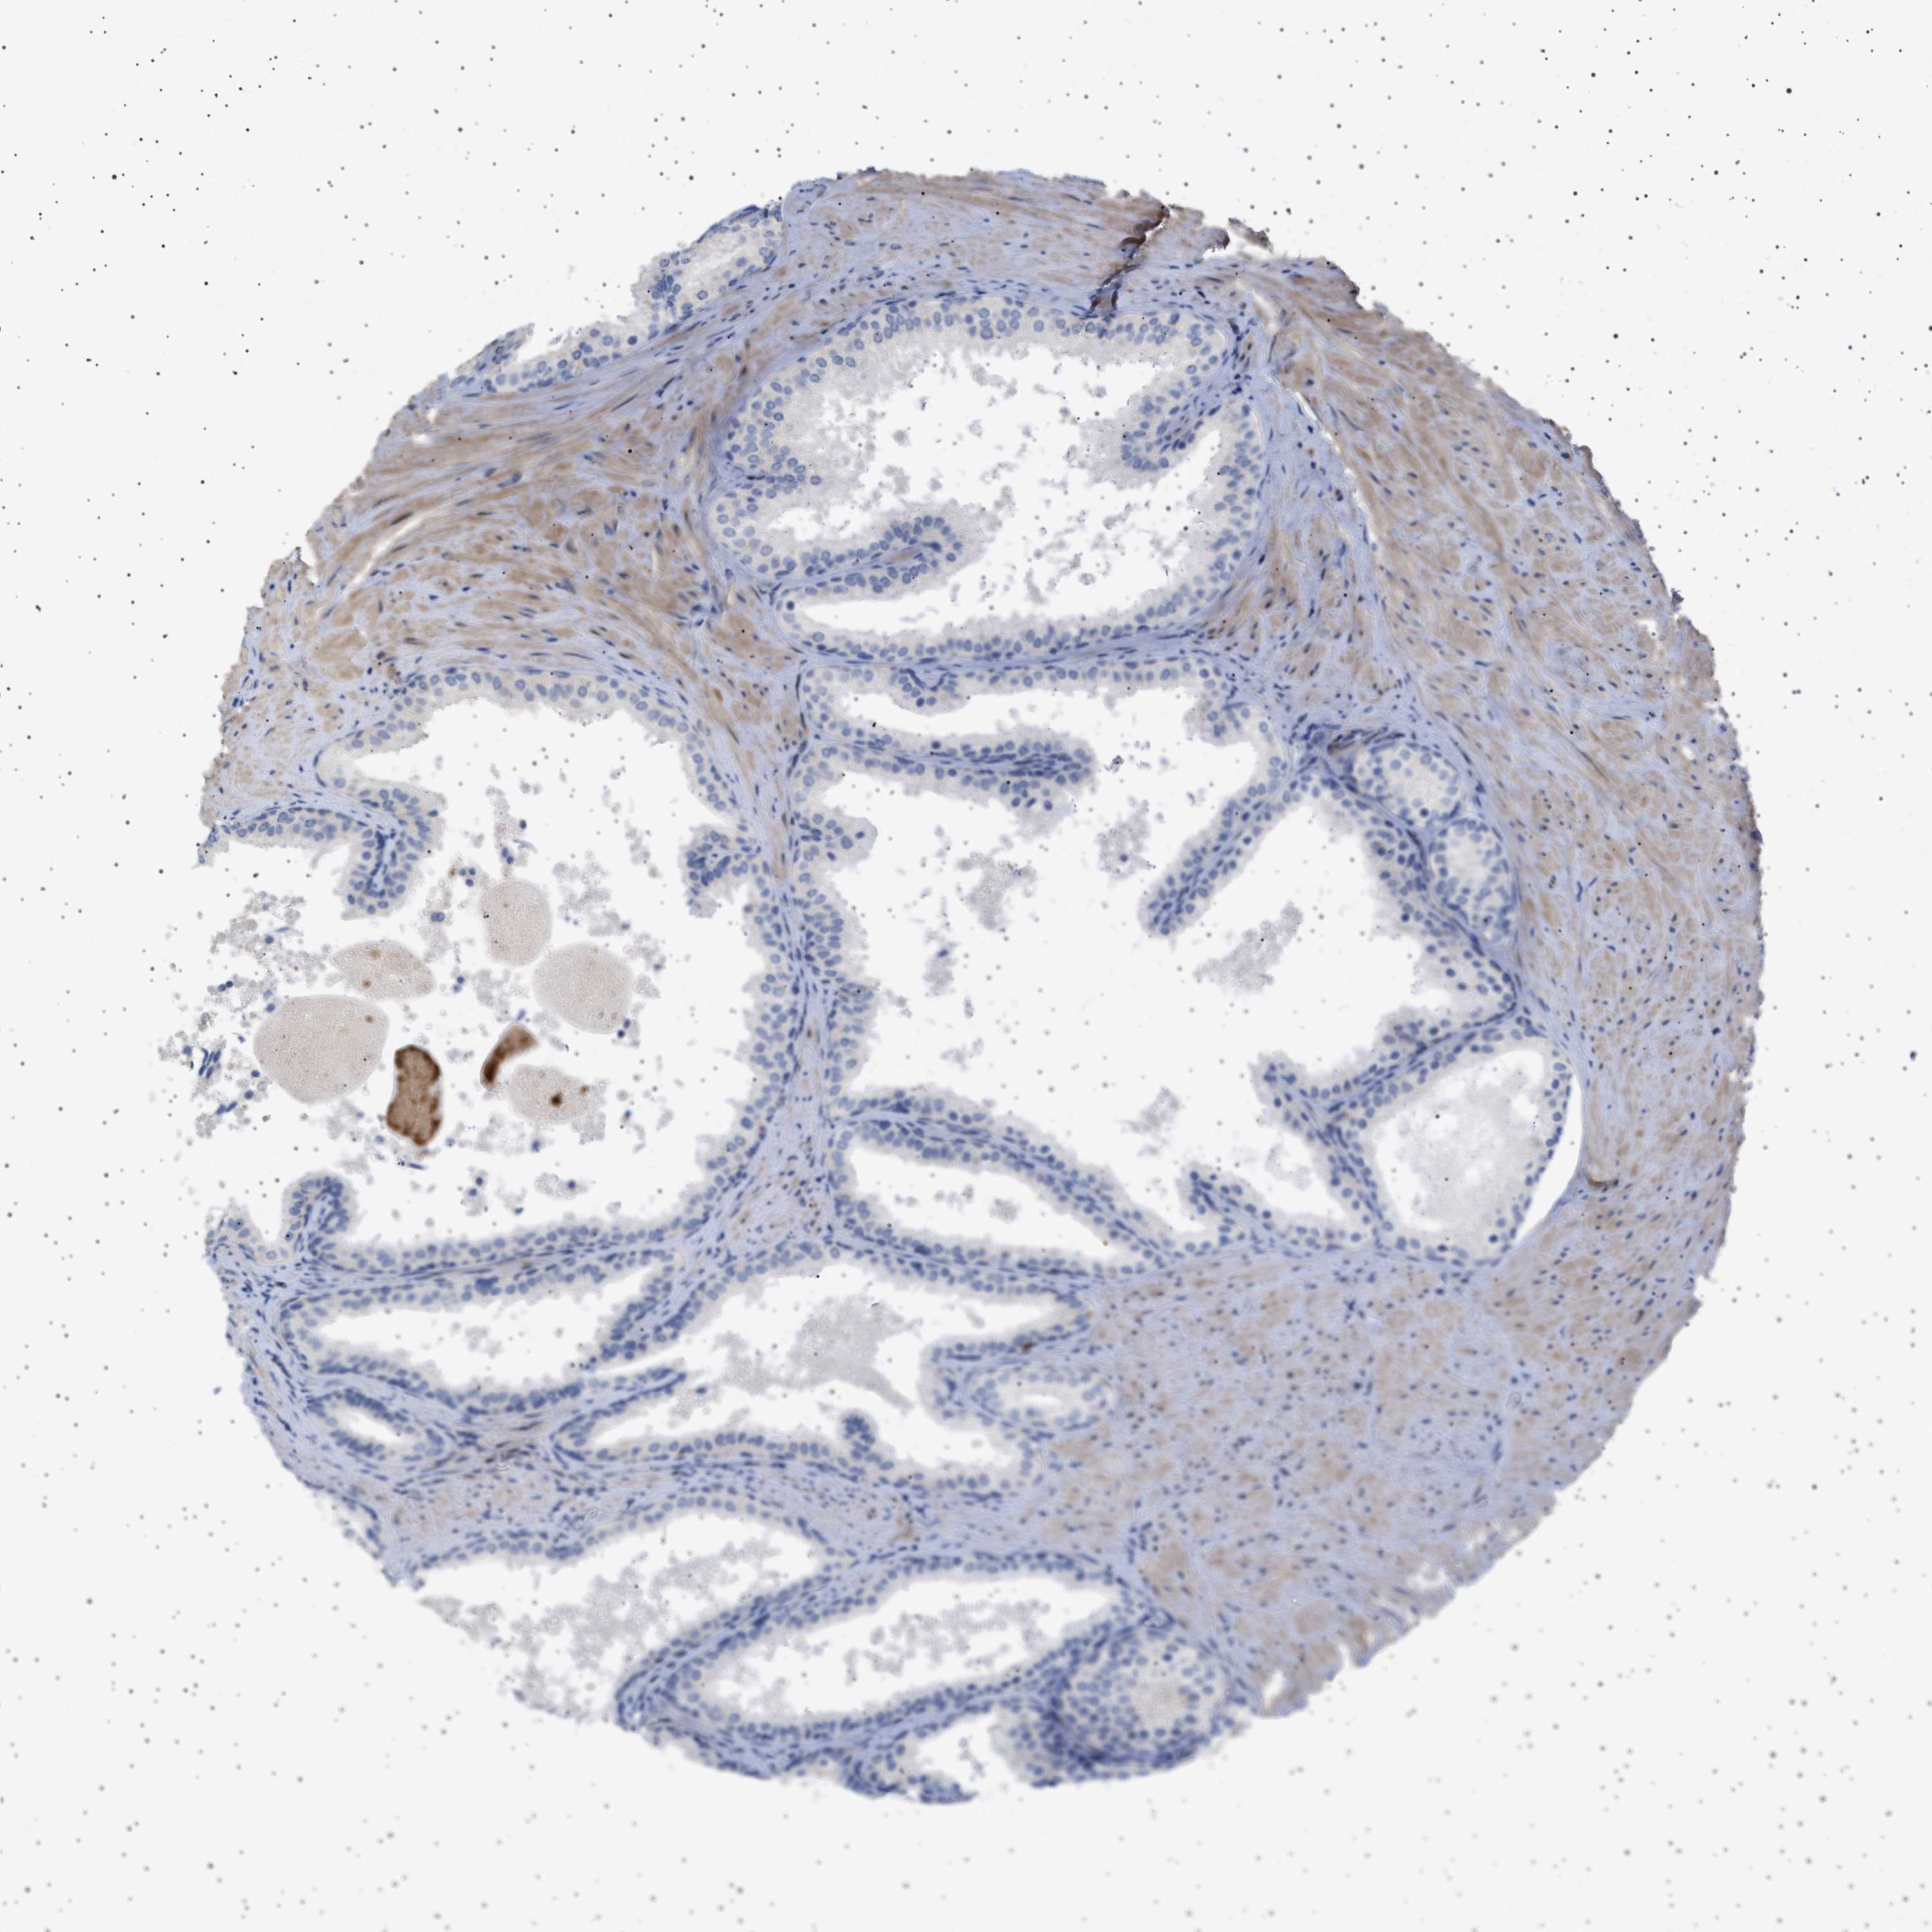

PROSTATE CANCER - Protein expressioni

A mouse-over function shows sample information and annotation data. Click on an image to view it in a full screen mode. Samples can be filtered based on level of antibody staining by selecting one or several of the following categories: high, medium, low and not detected. The assay and annotation is described here.

Note that samples used for immunohistochemistry by the Human Protein Atlas do not correspond to samples in the TCGA dataset.

Antibody stainingi

Antibody staining in the annotated cell types in the current human tissue is reported as not detected, low, medium, or high, based on conventional immunohistochemistry profiling in selected tissues. This score is based on the combination of the staining intensity and fraction of stained cells.

Each image is clickable and will lead to virtual microscopy that enables deeper exploration of all samples and also displays staining intensity scores, fraction scores and subcellular localization as well as patient and tissue information for each sample.

Antibody HPA018073

Staining

High

Medium

Low

Not detected

Intensity

Strong

Moderate

Weak

Negative

Quantity

>75%

75%-25%

<25%

None

Location

Nuclear

Cytoplasmic/membranous

Cytoplasmic/membranous,nuclear

Adenocarcinoma, High grade

Adenocarcinoma, Low grade